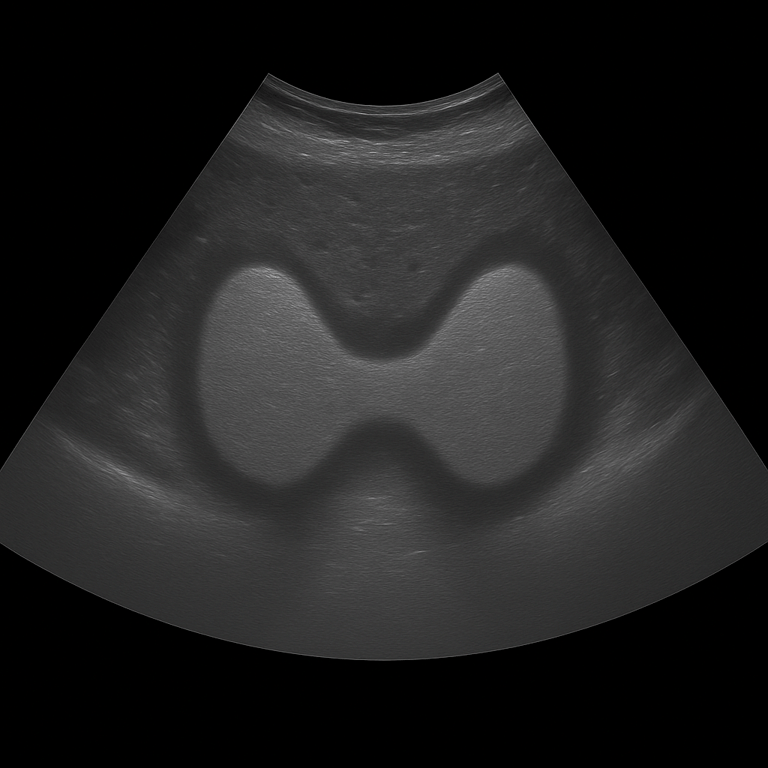

A thyroid ultrasound is used to assess the size, shape, tissue structure and any lumps or cysts of the gland. The examination is performed by a specialist in radiology and provides detailed real-time images of both lobes of the thyroid gland and the surrounding tissues in the neck. Thyroid ultrasound is used as the first-line method for investigating lumps, swelling, an enlarged thyroid gland or abnormal thyroid tests.

Unlike MRI and CT, which are rarely used for the soft tissues of the thyroid gland, ultrasound provides a high-resolution and direct image of the tissue. Ultrasound can also distinguish between solid and fluid-filled lesions and is often used to guide fine-needle aspiration (puncture) of suspicious nodules. It is a rapid, radiation-free method that provides an immediate visual basis for diagnosis.

The examination is performed while you lie on your back with your head slightly tilted back to expose the neck area. A gel is applied to the skin and the doctor moves the ultrasound probe over the thyroid gland. Both lobes and the isthmus (the connection between the lobes) are carefully assessed in longitudinal and cross-sectional views. If necessary, nearby lymph nodes in the neck can also be examined.